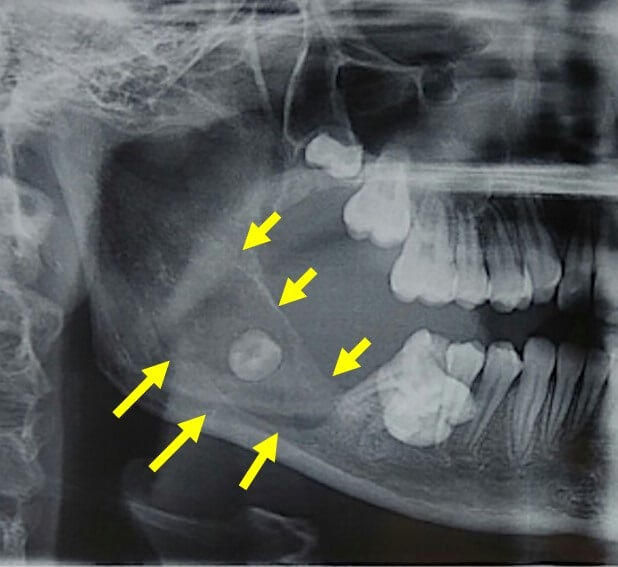

Рентгеновские снимки посттравматического остеомиелита челюсти: Медицинские случаи

Раздел: Образы вокруг